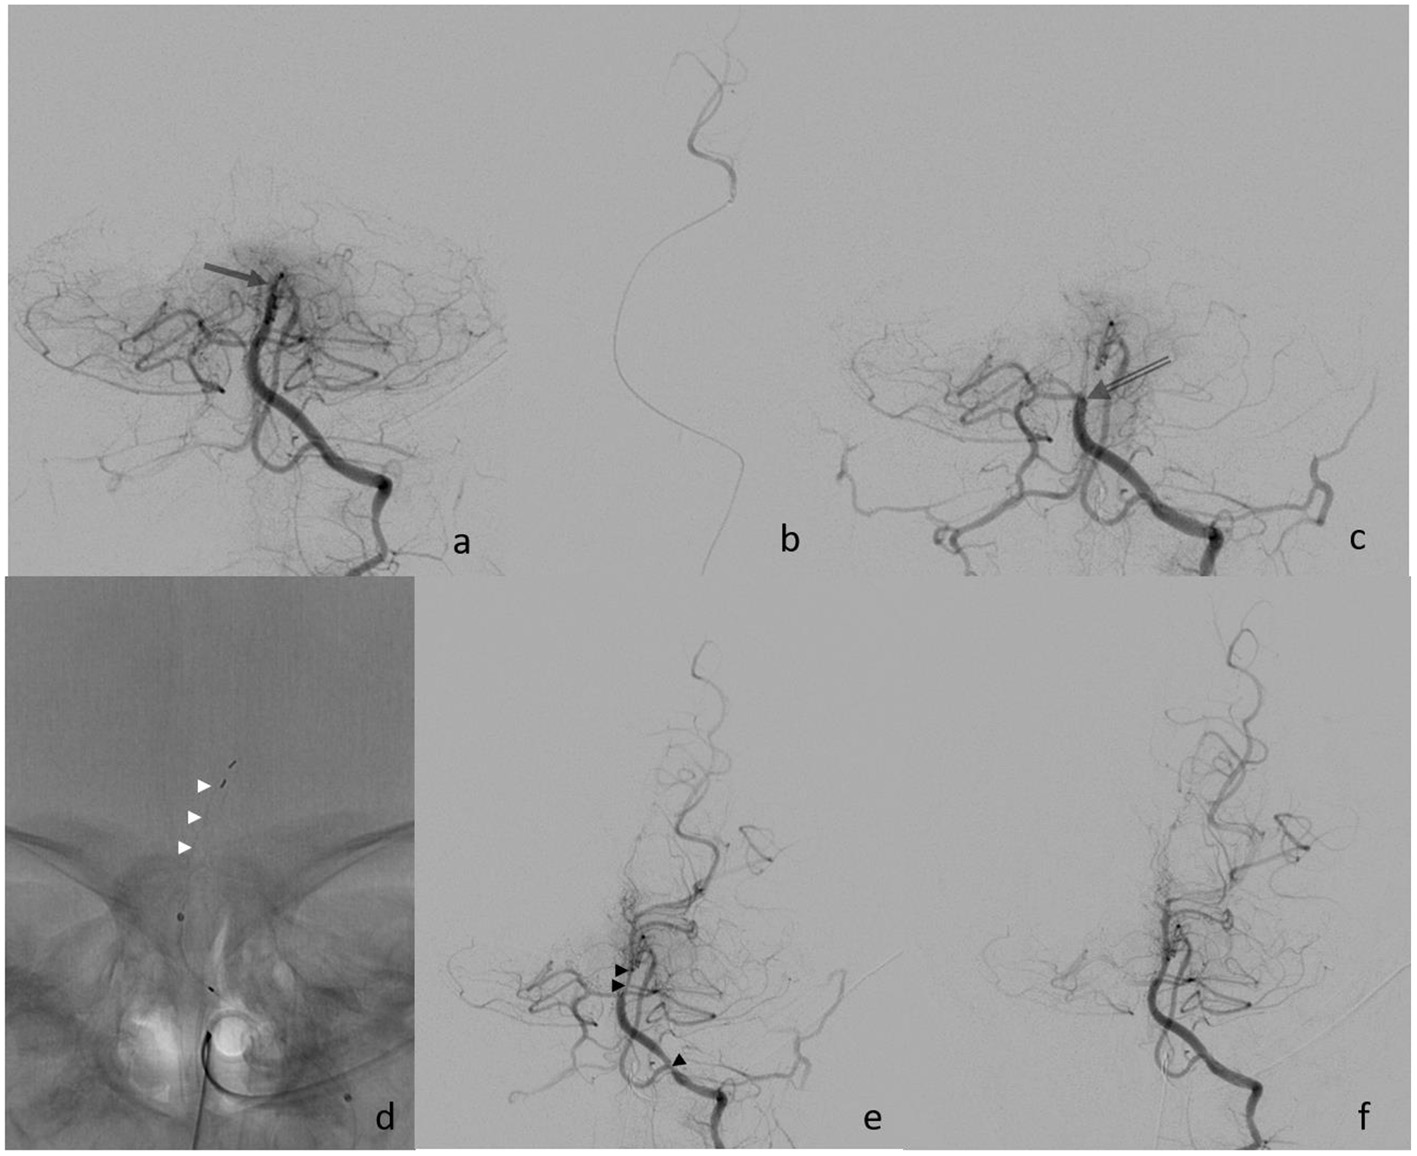

Figure 2

(a) Initial finding of distal basilar artery occlusion (arrow); (b) super selective injection into left PCA; (c) proximal occlusion after the 1st retriever maneuver (open arrow); (d) deployment of Preset device (white arrowheads); (e) finding after the 2nd retrieval with vasospasm (black arrowheads); and (f) final control after nimodipine infusion.

Eight hours after the symptom onset, the procedure started with the establishment of right femoral access using a 4-French (F) sheath. A 4F 100 cm vertebral shape catheter (Cordis Tempo, Cardinal Health, Dublin, Ireland) was used as a guiding catheter. The left vertebral artery (VA) showed a direct origin from the aortic arch and was then proximally catheterized. Bilateral subtraction angiography confirmed the distal occlusion of the hypoplastic BA (Figure 2). The BA was catheterized with a 156 cm Headway DUO microcatheter (Microvention, Aliso Vejo, CA, USA), guided by a manually pre-shaped Hybrid.008″ guidewire (Balt, Montmorency, France), and the thrombus passage was confirmed by a contrast injection showing a distal position in the left posterior cerebral artery (Figure 2b). MT was performed with a Catch Mini 3 ×15 mm (Balt, Montmorency, France) that was deployed within the occlusion. After 1 min, the stent retriever was pulled back toward the 4f-catheter and both devices were extracted under continuous aspiration. Subsequent catheterization of the left VA showed a persistent BA occlusion that was now more proximally located, and, therefore, a second MT maneuver was performed using a preset lite 3 ×20 mm (Phenox, Bochum Germany) device. Repeated catheterization of the left VA showed a completely recanalized but vasospastic BA. Within the next 5 min, a nimodipine infusion (0.1 mg) was applied through the catheter, followed by a final angiographic run that confirmed the visible improvement of the vasospasms and a patent BA 48 min after the start of the procedure, and 8 h after symptom onset.